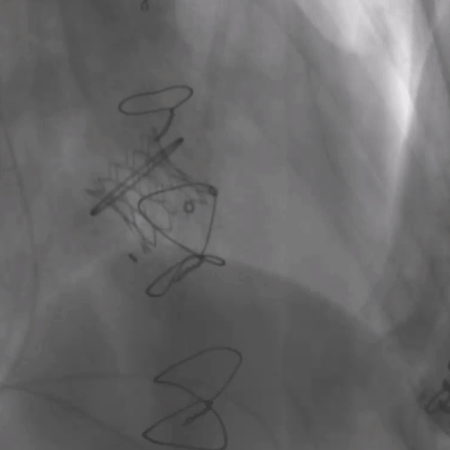

术前经详尽评估患者病情,通过CT重建测量瓣环直径、左室流出道面积。结合之前外科换瓣手术入路,决定采用经心尖途径行二尖瓣“瓣中瓣”手术。术中选用25# Renato®球扩式瓣中瓣,顺利通过心尖途径植入。手术过程顺利,几乎无出血。最终瓣中瓣植入位置理想,功能表现出色,左室造影及经食道超声观察无明显瓣中及瓣周反流。二尖瓣峰值流速由术前2.5m/s降至1.5m/s,平均跨瓣压差由11mmHg降至2.6mmHg。

毁损生物瓣瓣架结构 瓣环内径测量

瓣中瓣植入后无反流及瓣周漏